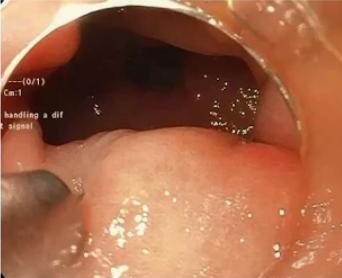

5.内镜治疗

若患者属于难治性、重度胃排空,可以考虑内镜治疗,包括:幽门内注射肉毒杆菌毒素、经口腔内镜下胃肌肉切开术、胃造口术、空肠造口术、幽门支架,部分示意图如下:

图4 经口腔内镜下胃肌肉切开术示意图